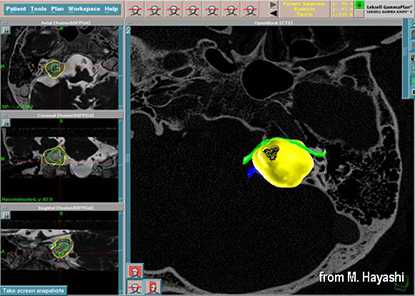

До начала радиохирургического лечения проводится обследование, позволяющее определить точное положение опухоли и прилегающих нервных образований. Выполняется трехмерная реконструкция, отображающая детальную микрохирургическую анатомию этой области. Для этой цели с помощью МРТ получают четкую визуализацию опухоли и нервов во внутреннем слуховом проходе и области мосто-мозжечкового угла.

С помощью планирующей системы Gamma Planи автоматической позиционирующей системывозможно проводить очень точное облучение опухоли (точность 0,5 мм), избегаяповреждения черепных нервов и других важных отделов мозга.

Преимуществами лечения на Гамма-ноже являются высокая степень сохранения функции лицевого нерва (в 98%) и слуха (в 80%). Полностью отсутствуют осложнения, связанные с открытой операцией (менингит, ликворея). Лечение проводится за один день. Госпитализации и послеоперационного восстановительного периода не требуется. Большинство пациентов возвращаются к своему обычному образу жизни на следующий деньпосле операции.

Слева - МРТпациентки М., 65 лет. Обратилась в радиохирургический центр МИБС с диагнозом-невринома правого VIII нерва. Проведено радиохирургическое лечение, доза по краю невриномы составила 13 Грей, в изоцентре опухоли 21,7 Грей.

Справа - контрольное МРТ через 1,5 года после операции. Отмечается уменьшение объёма опухоли на 47%.